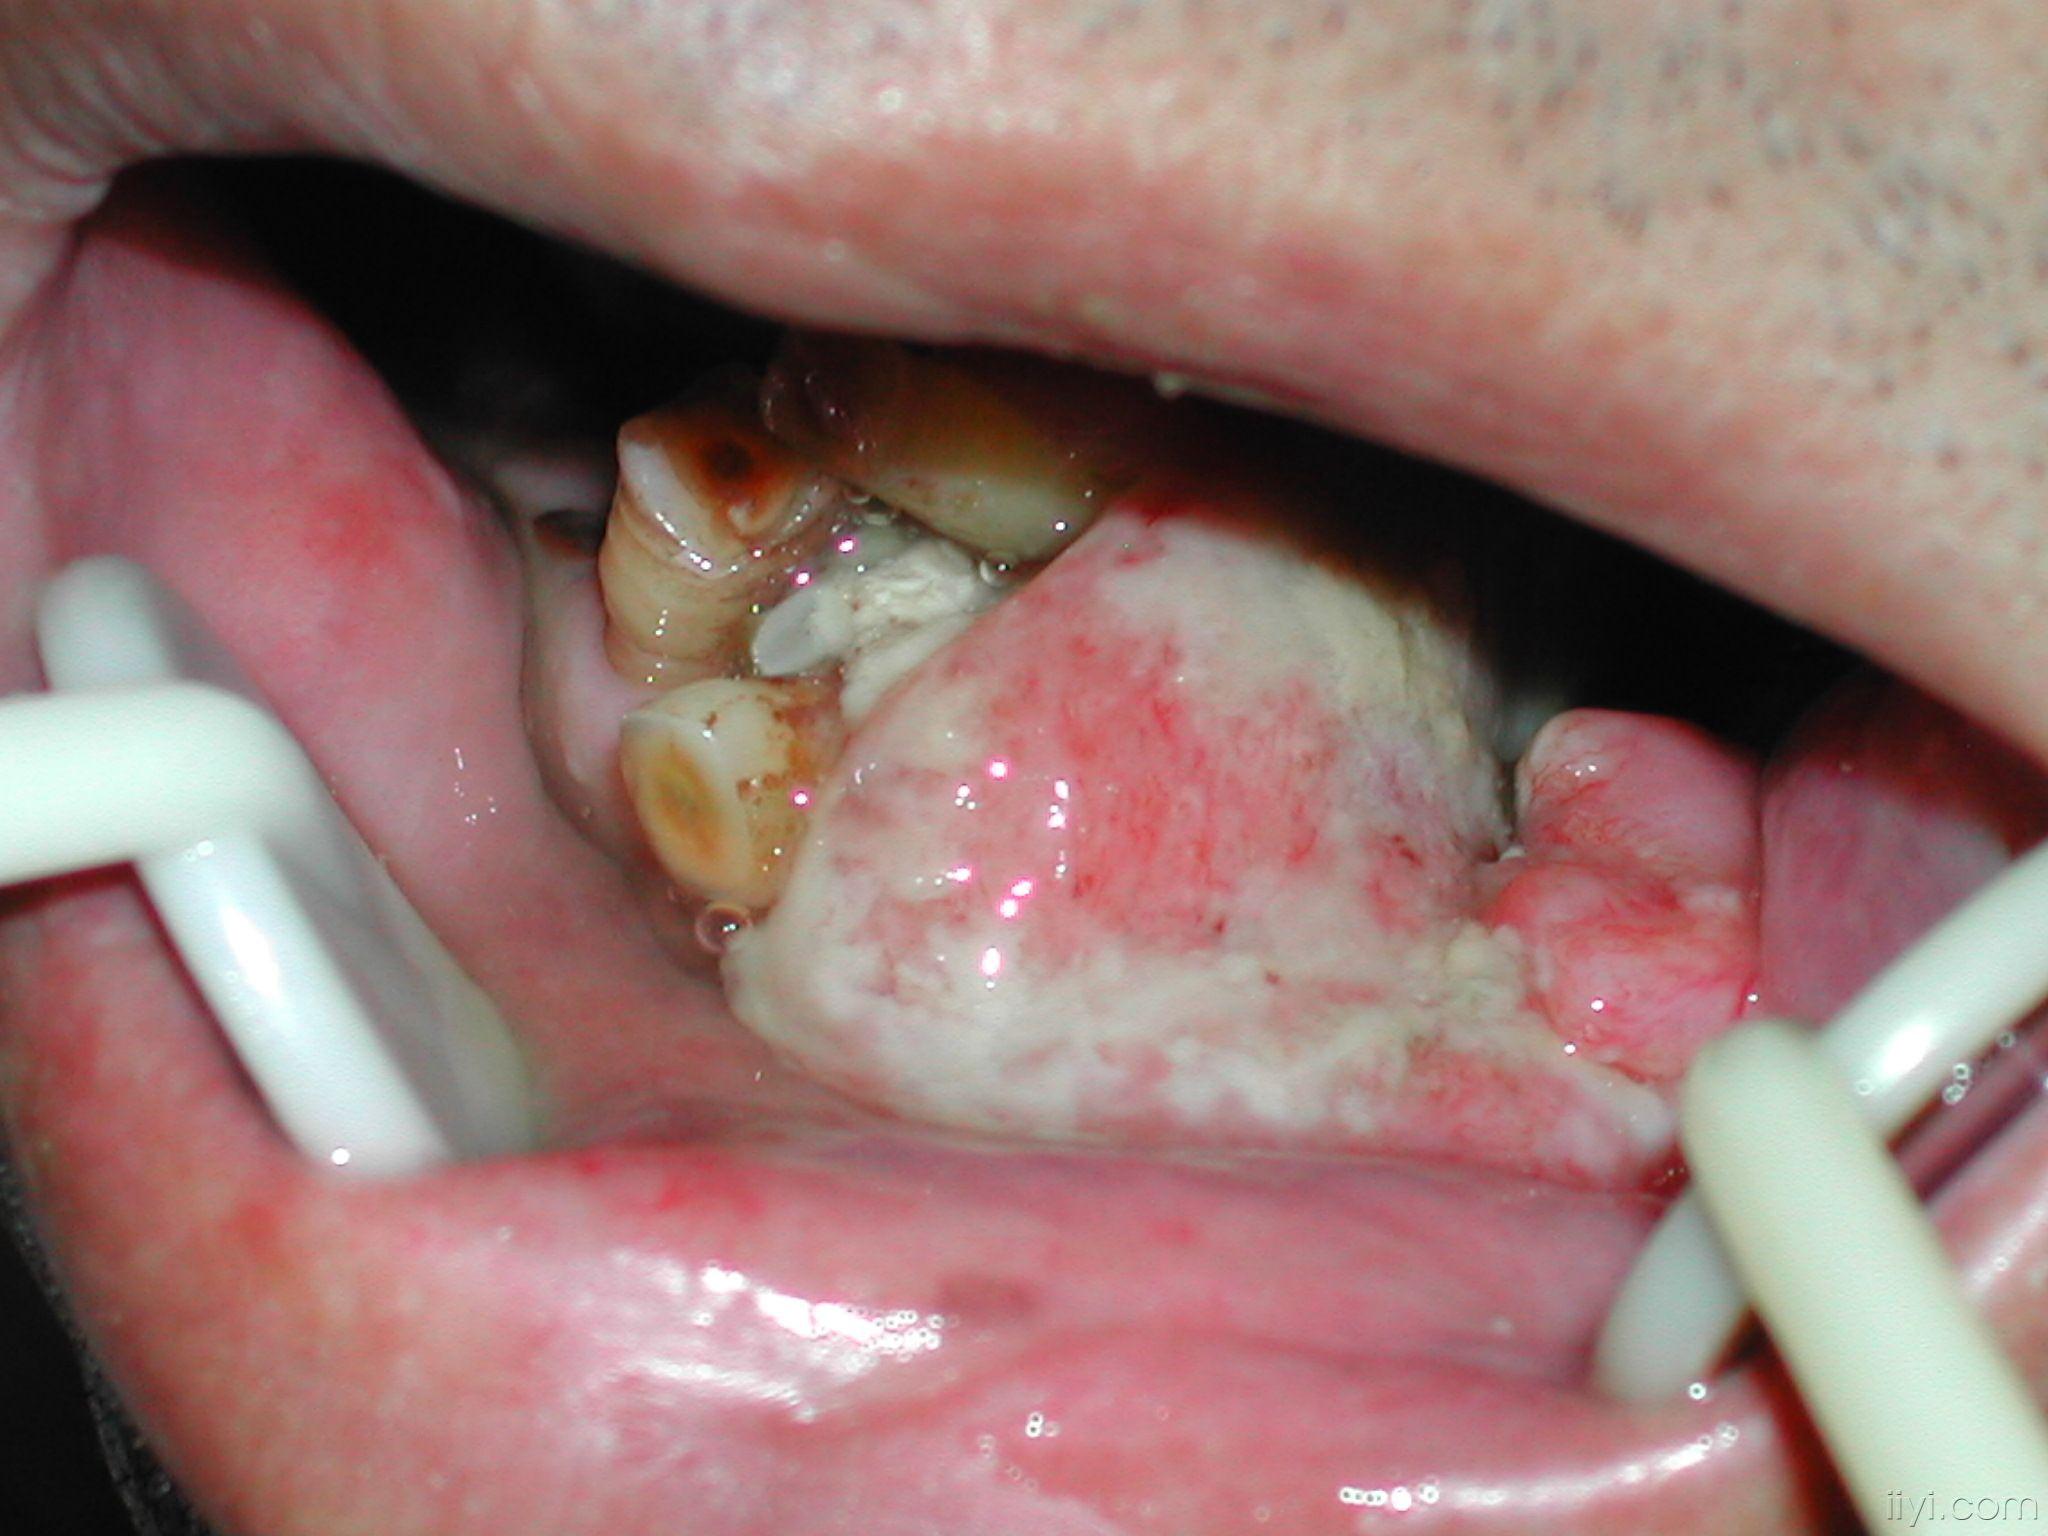

牙龈癌1例

牙龈癌早期症状图片(55)

牙龈癌

牙龈癌(图)

牙龈癌初期照片

牙龈癌早期症状图片(2)

典型病例05-牙龈癌 - 好大夫在线